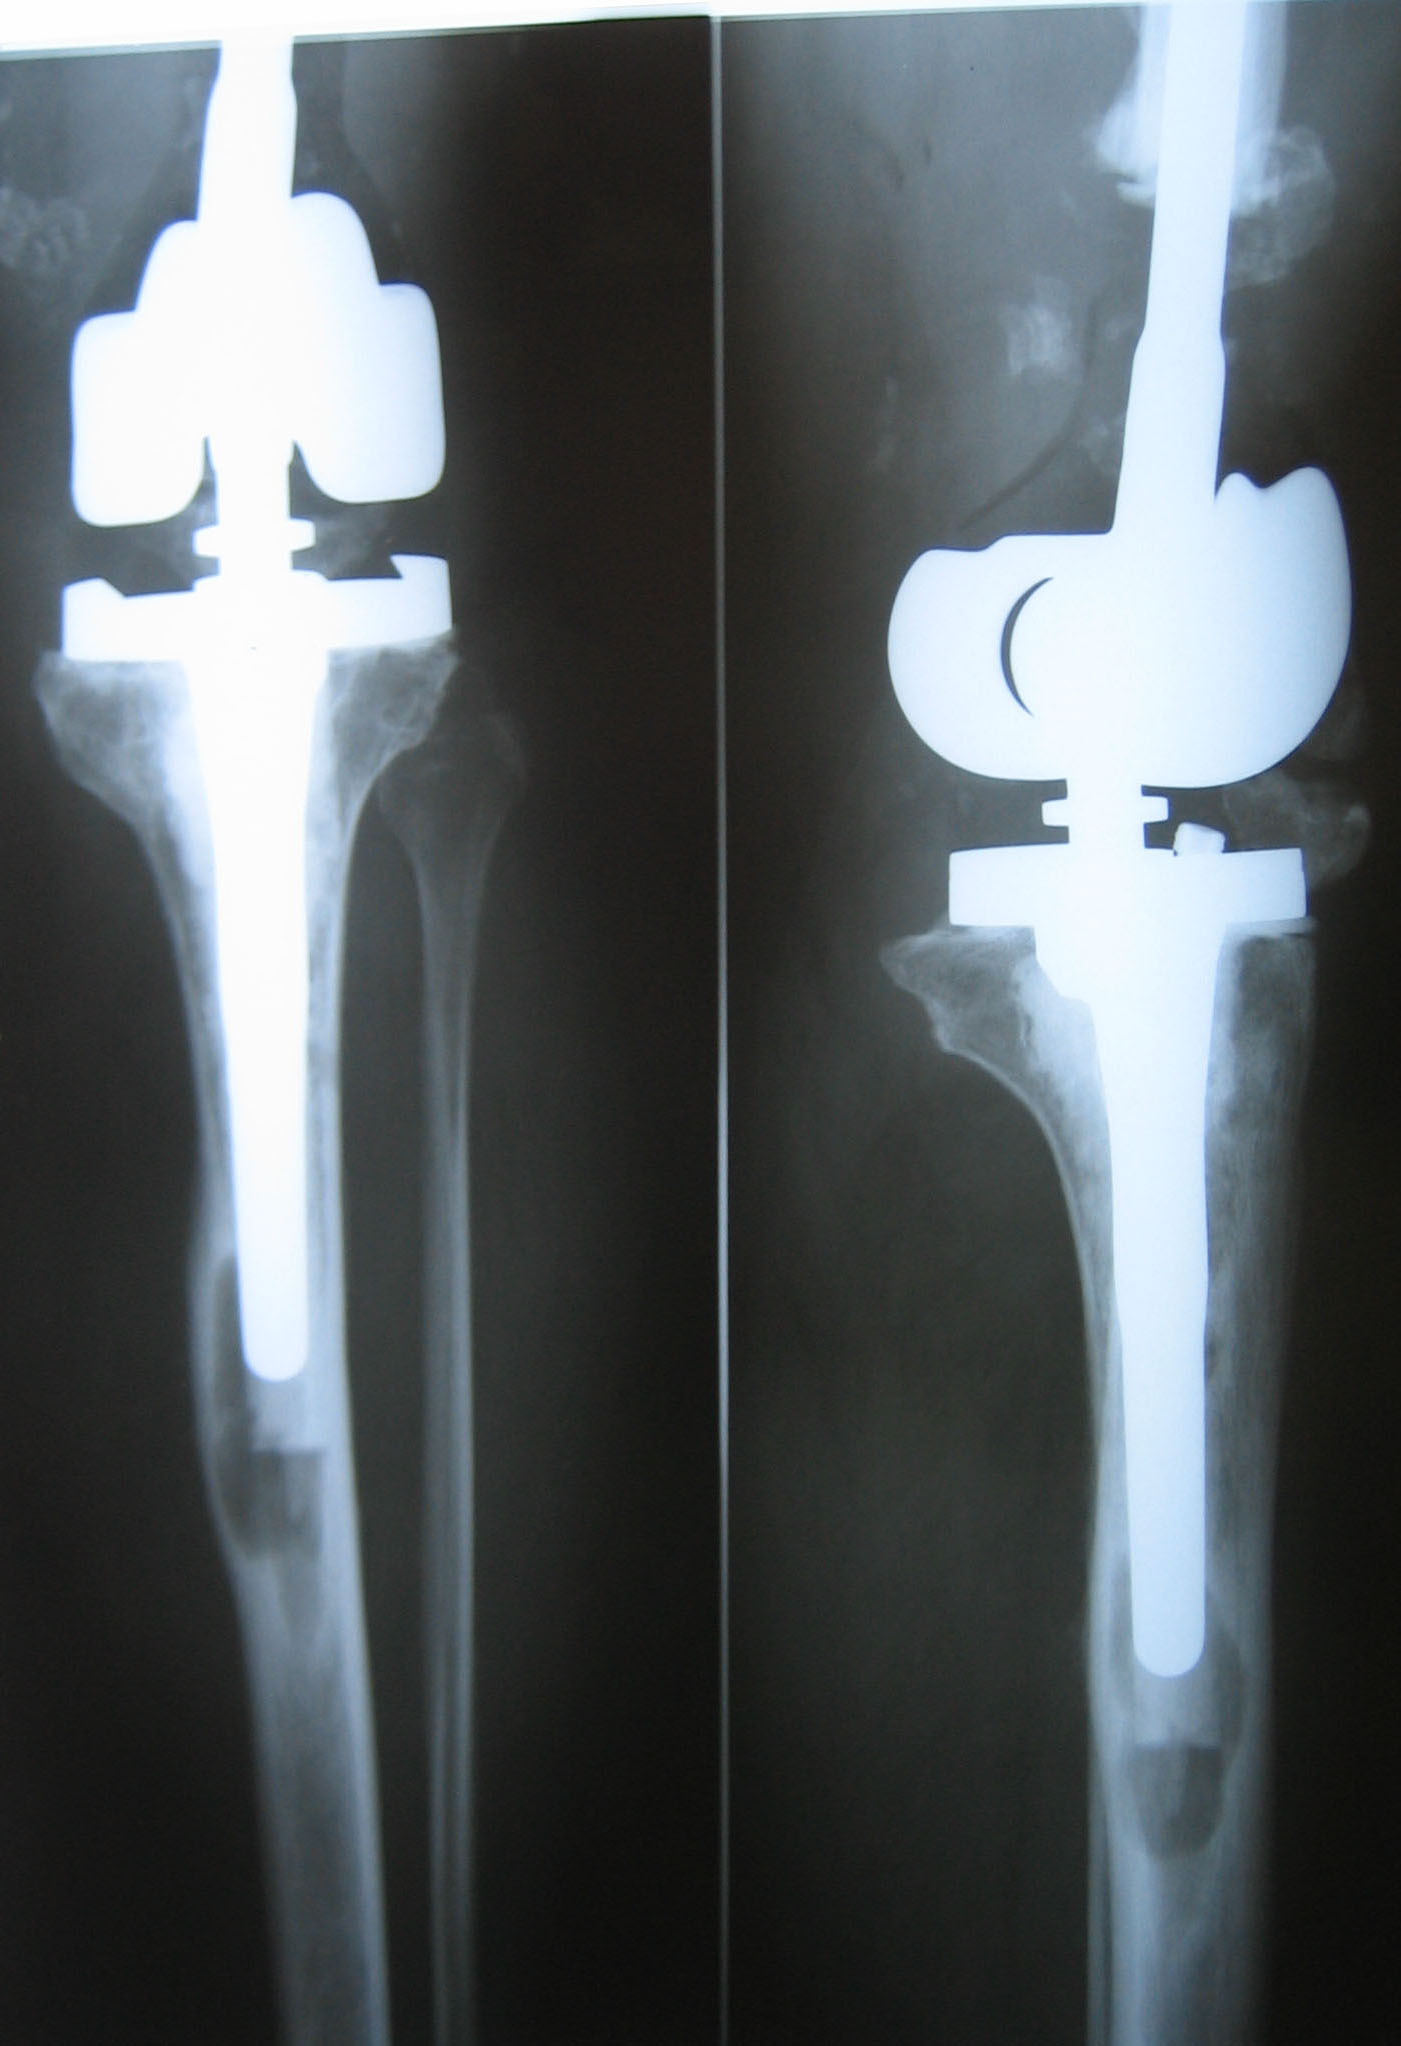

Женщина 40 лет. В 1998 г.по поводу саркомы дистального отдела бедра выполнено

эндопротезирование. В 2010 г. по поводу нестабильности - реэндопротезирование.

После этого колено ни дня не сгибалось, последний год - свищи. Промежуточных

О ререэндопротезировании речь не идет. Не видел бы проблем срастить бедро с

голенью с коррекцией длины, если бы не эти шкворни на цементе... Боюсь, при удалении

от кости, особенно бедренной, мало что останется.

1. Убрать железо из большеберцовой кости и макет мыщелков

бедра. Дебридемент.

2. Из бедра, как я понимаю, будет торчать 6-7 см арматуры. Есть мысль сделать самодельный

съемный спейсер с а/б  в виде полуцилиндра с пазом, как нарисовано на

схеме. Надеть его на стержень, ушить с дренированием. Снаружи - внешний

фиксатор в режиме компрессии месяца на два.

3. После этого спейсер извлечь, а дефект заместить либо с укорочением, внедрив

торчащий стержень в большеберцовую кость, либо используя костную крошку.

Имплант Безноска.